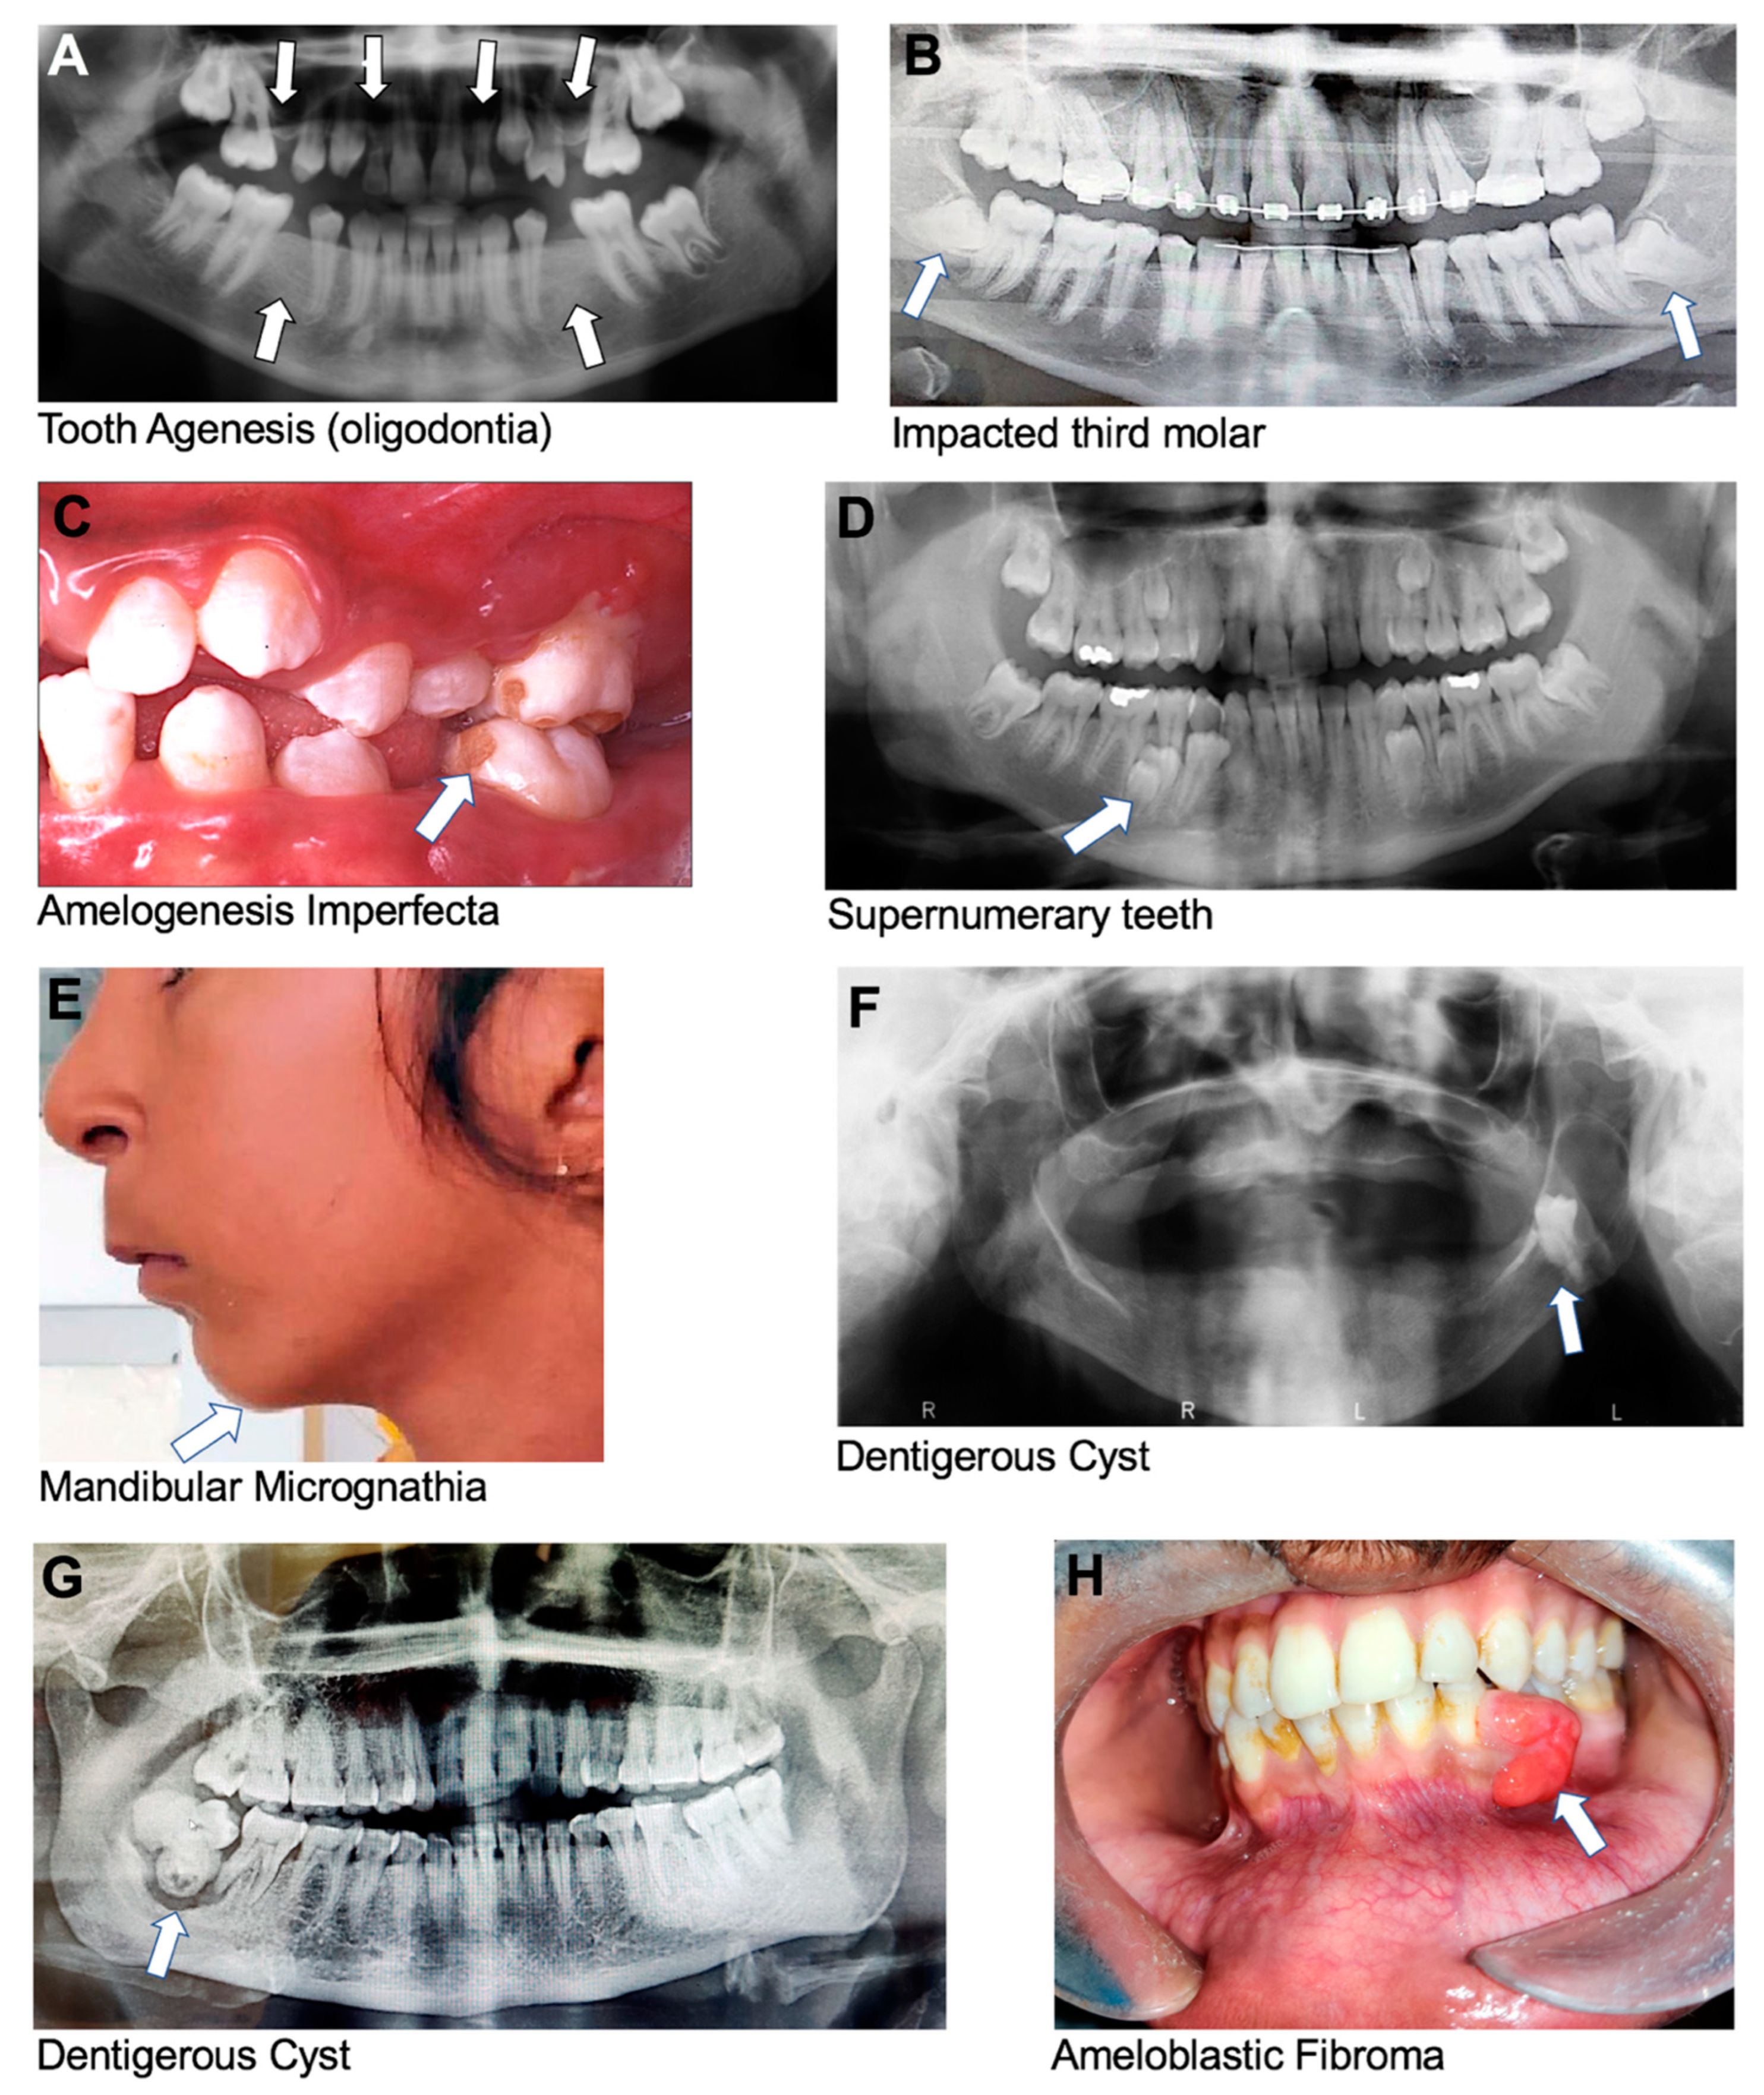

Figure 2. Oral conditions with strong genetic components as per our data analysis of retrieved articles. (A) Panoramic radiograph image of individual with oligodontia showing absence of six permanent teeth (excluding third molars). The following teeth are missing: 12, 15, 22, 25, 35, and 45, using the FDI numbering system (courtesy of Dr. Ariadne Letra). (B) Panoramic radiograph image of individual with impacted third molars. (C) Amelogenesis imperfecta showing enamel pitting with exposed dentin (courtesy of Dr. Cleverick (C.D.) Johnson). (D) Supernumerary teeth. (E) Mandibular micrognathia showing short lower jaw. (F,G) Dentigerous cyst (Image G is courtesy of Dr. Ritu Tiwari). (H) Ameloblastic fibroma at the lower left quadrant.

Oligodontia is a rare genetic condition that affects the development of teeth during childhood, characterized by six or more missing permanent teeth (Figure 2A), and is similar to hypodontia. Oligodontia can be caused by mutations in various genes involved in tooth development, like AXIN2, MSX1, and PAX9 [11,12,13,14,16,20,21,22,23]. MSX1 mutations impair the initial stages of dental development, while PAX9 mutations affect epithelial–mesenchymal interactions necessary for early tooth formation [12,19]. The condition can also be associated with other congenital syndromes, such as ectodermal dysplasia, Down syndrome, or familial cleft lip and palate, which are inherited in an autosomal-dominant pattern [20,21,22,23].

Impacted teeth are teeth that cannot emerge fully into the mouth due to a lack of space, an obstruction in their eruption path, and/or a misalignment resulting in a lack of an eruptive path; all these factors are influenced by genetics (Figure 2B). This can occur with any tooth in the mouth, but it most commonly affects the third molars, or wisdom teeth, and maxillary canines [44,45].

Amelogenesis imperfecta (AI) is a genetic disorder that affects the development of tooth enamel, which is the hard, protective, outer layer of teeth. This condition can affect both primary and permanent teeth, and it can result in teeth that are discolored, weak, and prone to fracture [46]. There are several types of AI, each with its own specific pattern of inheritance and symptoms. The disorder can be inherited in an autosomal-dominant, autosomal-recessive, or X-linked manner, depending on the specific genetic mutation involved [28]. Mutations in the genes AMELX, ENAM, MMP20, KLK4, and DLX3 are reported to be associated with the development of AI [9,28,46,47]. Clinically, teeth affected by AI may be yellow or brown, have rough or pitted surfaces, or be abnormally small or misshapen (Figure 2C). Teeth affected by this condition may also be sensitive to temperature and pressure.

3.1.6. Supernumerary Teeth

Micrognathia is a congenital medical condition characterized by an abnormally small mandible or maxilla (Figure 2E). Micrognathia can be caused by various factors, including genetic abnormalities, or problems with the growth and development of the jaw bones during fetal development [62]. It can also occur due to environmental factors, such as exposure to certain medications or toxins during pregnancy [62]. Mutations in more than fifteen different groups of genes have been associated with the development of micrognathia [62]. Micrognathia can occur in isolation or as part of a symptom of other craniofacial conditions. For example, micrognathia is often seen as part of the Pierre Robin sequence that is mostly caused by mutations in SOX9 [62,63]. The Pierre Robin sequence occurs in about 1 per 8500 live births [64]. It is called a sequence due to a sequence of events that occur during fetal development—the mandible does not grow enough, which causes the tongue to be pushed back, preventing the secondary palatal shelves from developing, leading to a failure of the palatal bones to close and remain separated in the midline. Babies born with the Pierre Robin sequence may have difficulty breathing, feeding, and/or sleeping. Symptoms can range from being very mild to quite severe, including an underdeveloped mandible, cleft palate, glossoptosis, and airway obstruction [64].

Dentigerous Cyst

Ameloblastic Fibroma

Keratocystic Odontogenic Tumor (KCOT):